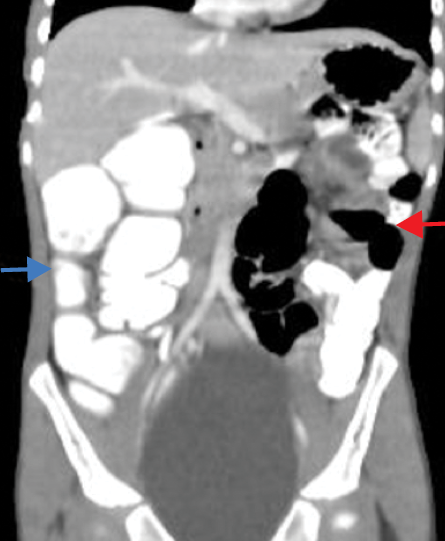

The contrast-enhanced computed tomography (CECT) abdomen findings were as follows: The D3 segment of the duodenum was seen to cross to the left side with the duodeno-jejunal junction in its expected location. The superior mesenteric arter-superior mesenteric vein (SMA-SMV) relationship was maintained with the SMV lying on the right side of SMA. The small bowel loops were predominantly on the left side of the abdomen, and the entire colonic loops were positioned on the right side of the abdomen [Figure 1]. The ileocecal junction (ICJ), cecum, and appendix were noted in the right lumbar region [Figure 2]. The inferior mesenteric artery was seen coursing to the right side of the midline, rather than its normal left-sided course [Figure 3]. A tubular cystic lesion was observed in relation to the small bowel loops on the left side of the abdomen [Figure 4]. Intrabdominal solid organs were essentially normal, with a normal situs.

Figure 2: Coronal sections of contrast-enhanced computed tomography abdomen showing the position of the ileocecal junction (red arrow), cecum and appendix (blue arrow) in the right lumbar region.